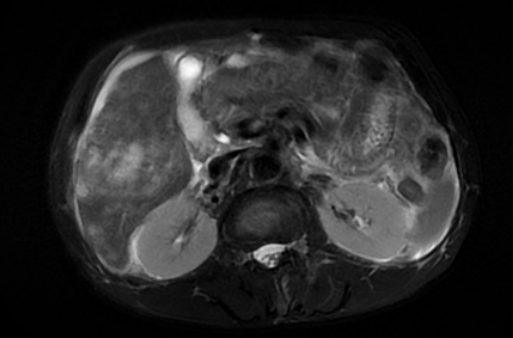

近日,一场与死神的赛跑在我院肿瘤科悄然展开。65岁的阙先生,有高血压病史,中午工地劳作突然出现剧烈腹痛,同时伴有头晕恶心呕吐等症状,随后被家人紧急送往我院急诊科。经过一系列急诊检查,血压73/52mmHg,心率112次/分,血氧饱和度92%,腹部CT考虑肝右叶肿瘤破裂出血合并腹盆腔积液;急诊B超提示肝实质性占位,考虑肝癌。病情危急,紧急转入我院肿瘤科。

肝癌破裂出血是临床上的急危重症,多发病急,病情凶险,愈后较差。如果不进行及时救治,死亡率极高。危急之下,县中医院肿瘤科立即进行科内会诊并达成一致结论,考虑到患者年龄较大,肝肿瘤巨大,出血量多,随时有生命危险,且不具备转运条件,需立刻进行急诊介入栓塞止血。接诊医师罗时腾立即完善术前准备,并为患者进行急诊调血;院长助理、主任医师周文辉立即同患者家属沟通并根据患者自身情况制定详细手术方案,为确保手术万无一失,周院长还紧急联系吉安市中心人民医院肿瘤科杨信太主任现场手术指导。患者被快速送入介入室。杨信太主任和我院肿瘤科团队根据手术方案,对多支可能存在出血的血管进行筛选,最终在造影中发现出血“责任血管”,并立即“超选”责任血管后进行栓塞治疗。栓塞后造影,出血血管被精准栓塞。